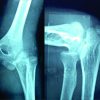

A 10-year-old previously healthy male presented to the orthopedics outpatient department with complaints of the left shoulder weakness and restricted range of motion. One month earlier, he sustained a WHO category 2 dog bite on the left calf while playing; following which he received wound care and PEP at a local primary health center [6]. His vaccination schedule included three intradermal doses of PVRV (Fig. 1 and 2) administered on days 0, 3, and 7. The first and last doses were administered in the left deltoid, while the second dose was given in the right deltoid.